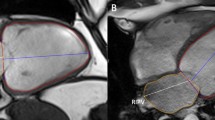

Pre-procedural a LA and b SA cine MRI acquisition, along with automatic outline of endocardial (yellow) and epicardial (green) contours in the acquired SA and LA images. c Display of regional volume curves expressed as a percentage of the total cardiac cycle for each of the 16 segments of the American Heart Association LV model

CMR imaging: Computer-assisted interventional system [3, 25] Following the pre-procedural CMR acquisition, a fully automatic slice-by-slice segmentation and propagation of the endocardial and epicardial LV borders, at each time point in the stack of SA and three LA SSFP cine images, was computed. The epicardial and endocardial surfaces of the LV are extracted automatically using a model-based segmentation algorithm [2]. Spatial contour re-positioning is used to correct for any misalignment of the segmented SSFP endocardial and epicardial borders (Fig. 1a, b). Any contours found in any slices where the mitral valve is visible are excluded from the segmentation. The LV segmentation step has been previously quantitatively evaluated on 14 CRT patients and compared to a ground truth expert manual segmentation [25]. The average Dice coefficient of myocardial tissue for all slices in all procedures was 88.0% indicating the clinical validity of the approach. Errors were attributed to low-quality images caused by motion artefacts. Although the segmentation is fully automatic, the clinician has the option to manually edit the result, by clicking on the automatically detected contours in the MR slices, if they are not satisfied with the automatic output. This was unnecessary in 8 of the 14 cases, small changes were made in 5, and larger changes were needed in only 1 case. The average Dice coefficient was 97.0% between the automatic and edited segmentations, indicating that the manual editing is a minor part of the process. The automatic segmentation, along with any possible clinical amendment, takes only a couple of minutes to perform and hence does not disrupt or lengthen the clinical procedure.

Data were analysed using offline diagnostic software circle CVI42 (version 5.6.4; circle cardiovascular imaging, Canada). Following the pre-procedural CMR acquisition, a fully automatic slice-by-slice segmentation and propagation of the endocardial and epicardial LV borders in the stack of SA and 4-chamber LA SSFP cine images is computed. Manual contour re-positioning is allowed to correct for any misalignment of the segmented SSFP endocardial and epicardial borders (Fig. 2a). Any slices in the stack found beyond the LV are excluded from the LV automatic segmentation (Fig. 2c). Following this, a reference contour for diastole and systole is automatically drawn with the opportunity for manual correction. The software then computes EDV, ESV, SV and EF parameters (Fig. 2b) as well as the global volume curve over the cardiac cycle (Fig. 2d).